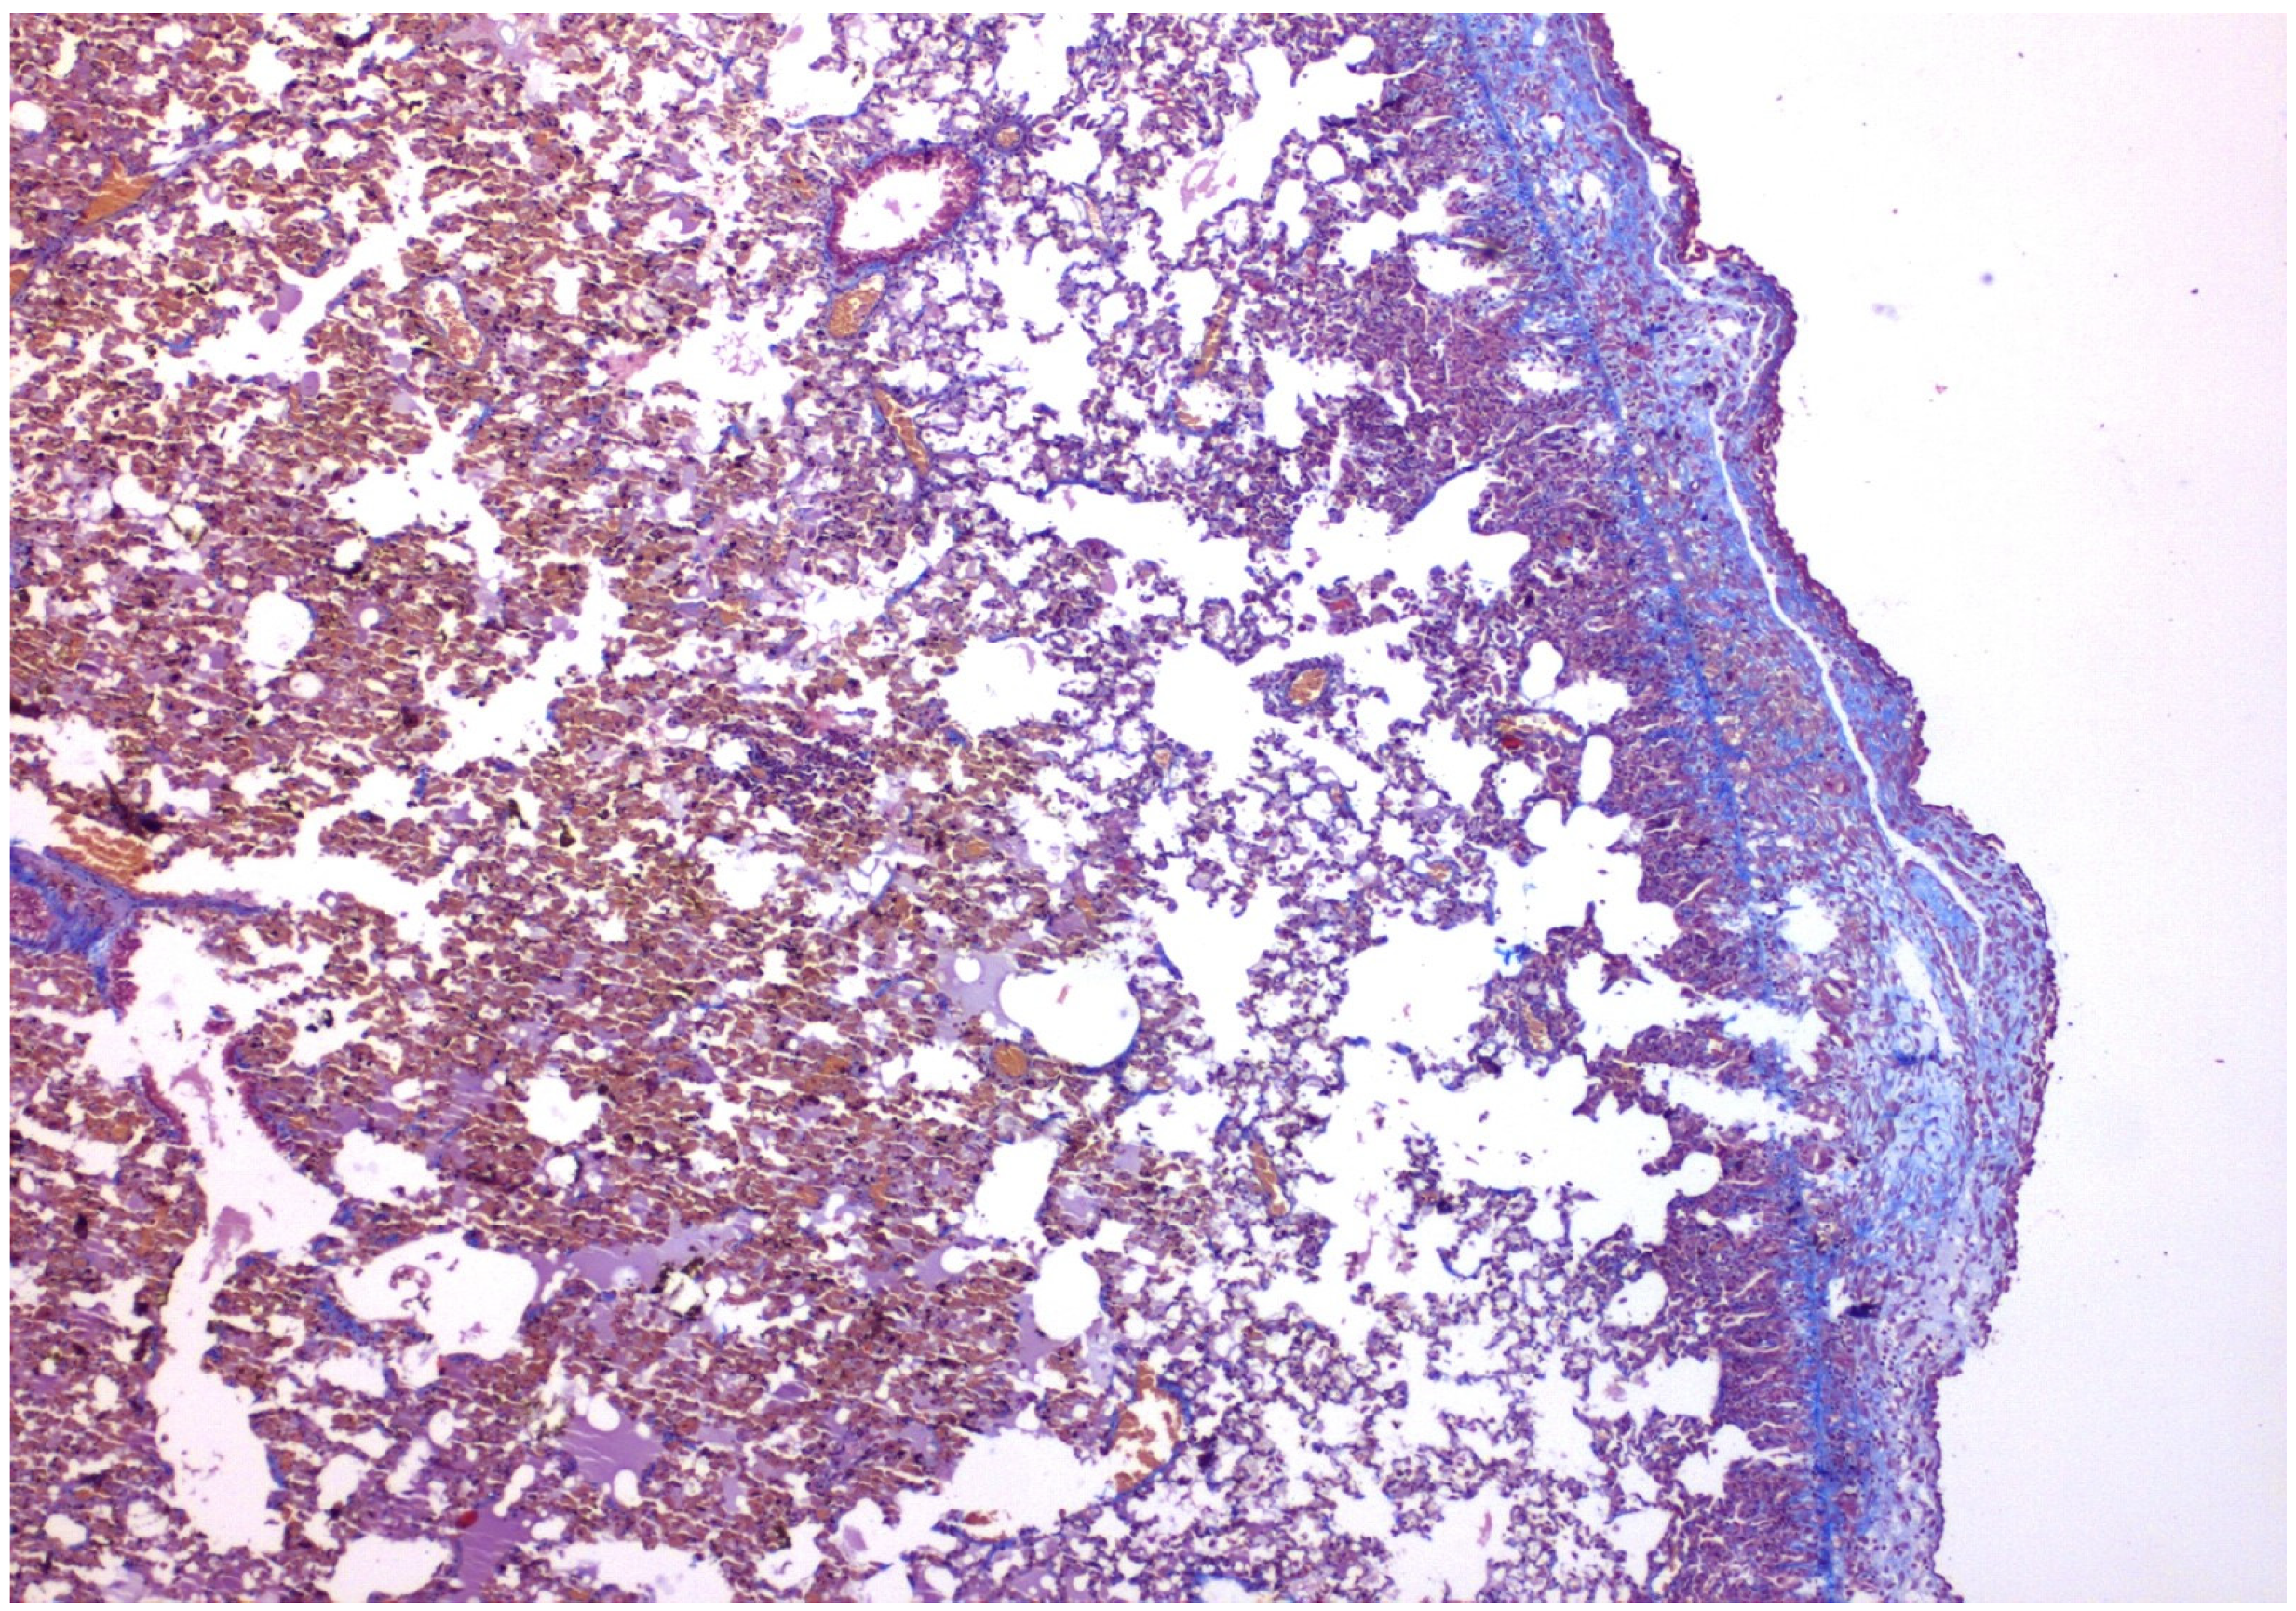

- With talc, there was a statistically significant difference in the inflammation provoked in 6 days compared to 3 days regarding parietal pleura (p = 0.002) (Figure 11); regarding visceral pleura, this could not be measured, as inflammation was high in both groups (grade II–III).